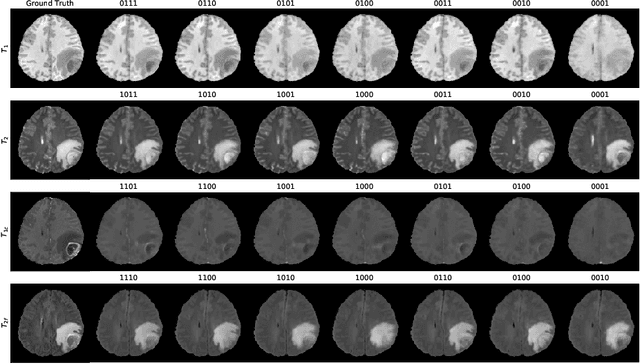

Abstract:Magnetic resonance imaging (MRI) is being increasingly utilized to assess, diagnose, and plan treatment for a variety of diseases. The ability to visualize tissue in varied contrasts in the form of MR pulse sequences in a single scan provides valuable insights to physicians, as well as enabling automated systems performing downstream analysis. However many issues like prohibitive scan time, image corruption, different acquisition protocols, or allergies to certain contrast materials may hinder the process of acquiring multiple sequences for a patient. This poses challenges to both physicians and automated systems since complementary information provided by the missing sequences is lost. In this paper, we propose a variant of generative adversarial network (GAN) capable of leveraging redundant information contained within multiple available sequences in order to generate one or more missing sequences for a patient scan. The proposed network is designed as a multi-input, multi-output network which combines information from all the available pulse sequences, implicitly infers which sequences are missing, and synthesizes the missing ones in a single forward pass. We demonstrate and validate our method on two brain MRI datasets each with four sequences, and show the applicability of the proposed method in simultaneously synthesizing all missing sequences in any possible scenario where either one, two, or three of the four sequences may be missing. We compare our approach with competing unimodal and multi-modal methods, and show that we outperform both quantitatively and qualitatively.